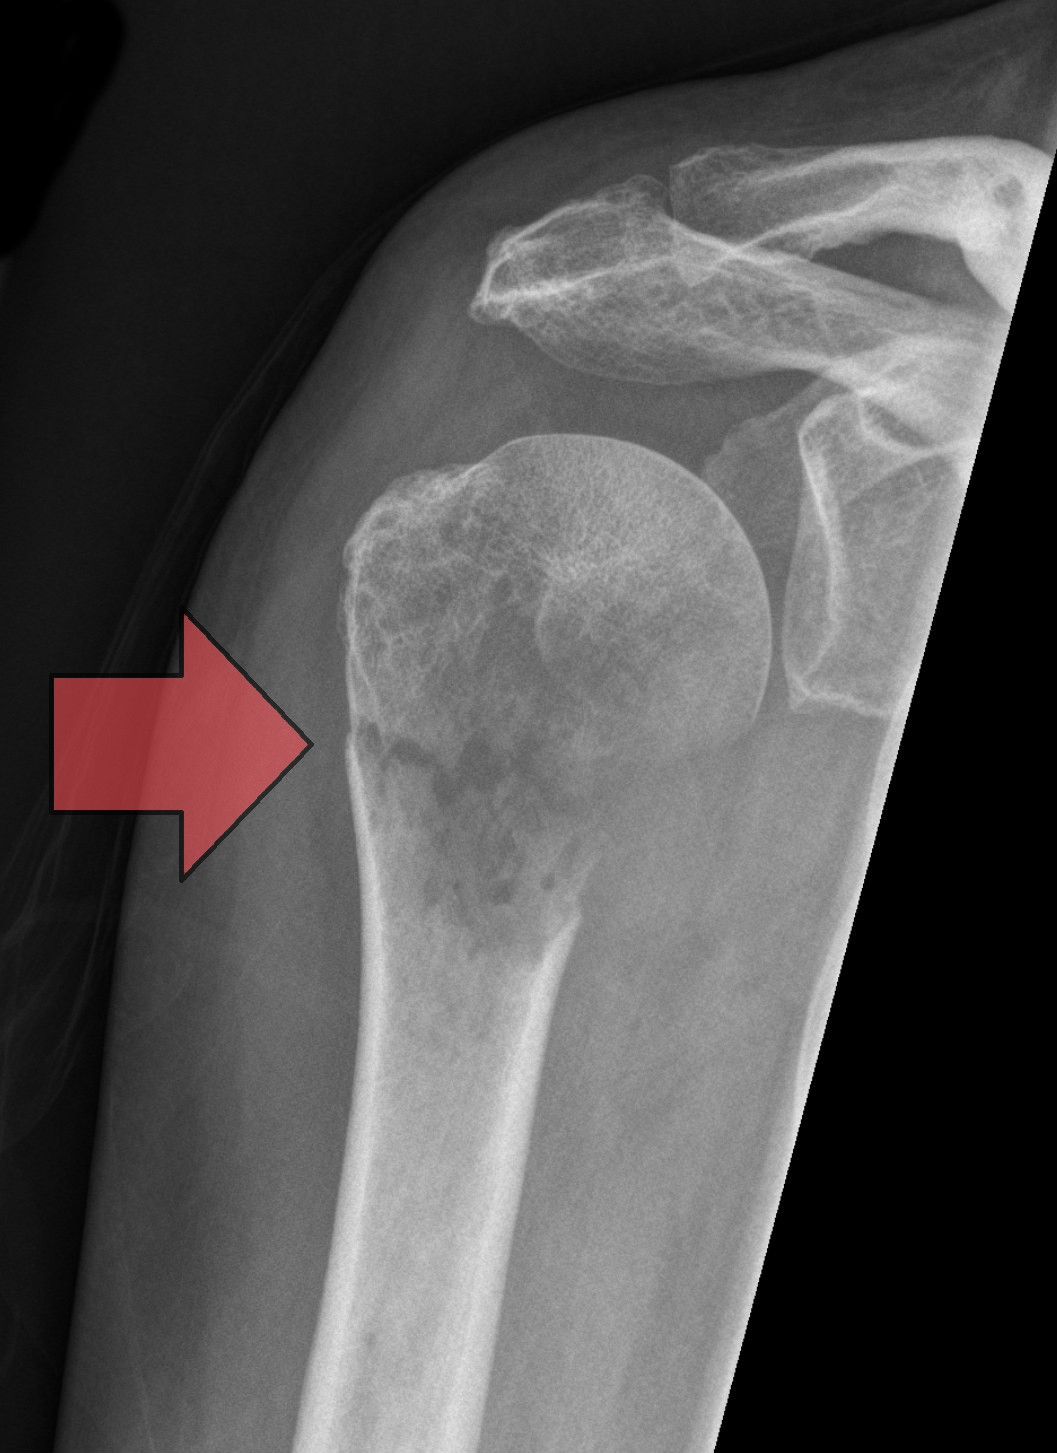

Dr. Italiya has extensive expertise in trauma care, joint replacement surgeries (knee & hip), fracture management, arthritis treatment, and spine-related conditions. His approach focuses on long-term recovery and functional restoration rather than temporary pain relief.

Specialized orthopedic trauma care for fractures, injuries, and medico-legal cases with immediate medical attention.